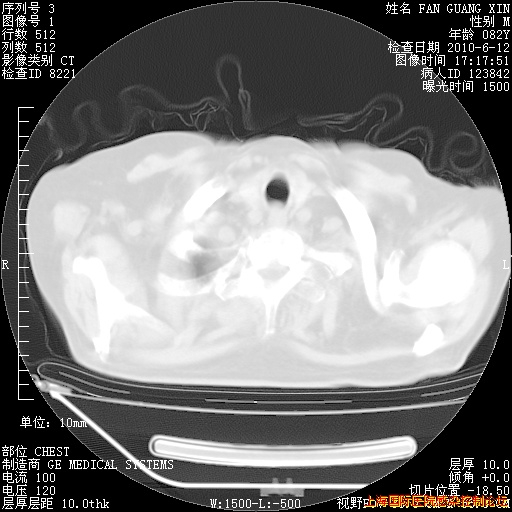

补发6月12日肺部CT肺窗

6月12日肺窗

6月12日纵膈窗

整整相隔30天的肺部CT好像有所好转啊。甲强龙减量第3天,需要观察体温。